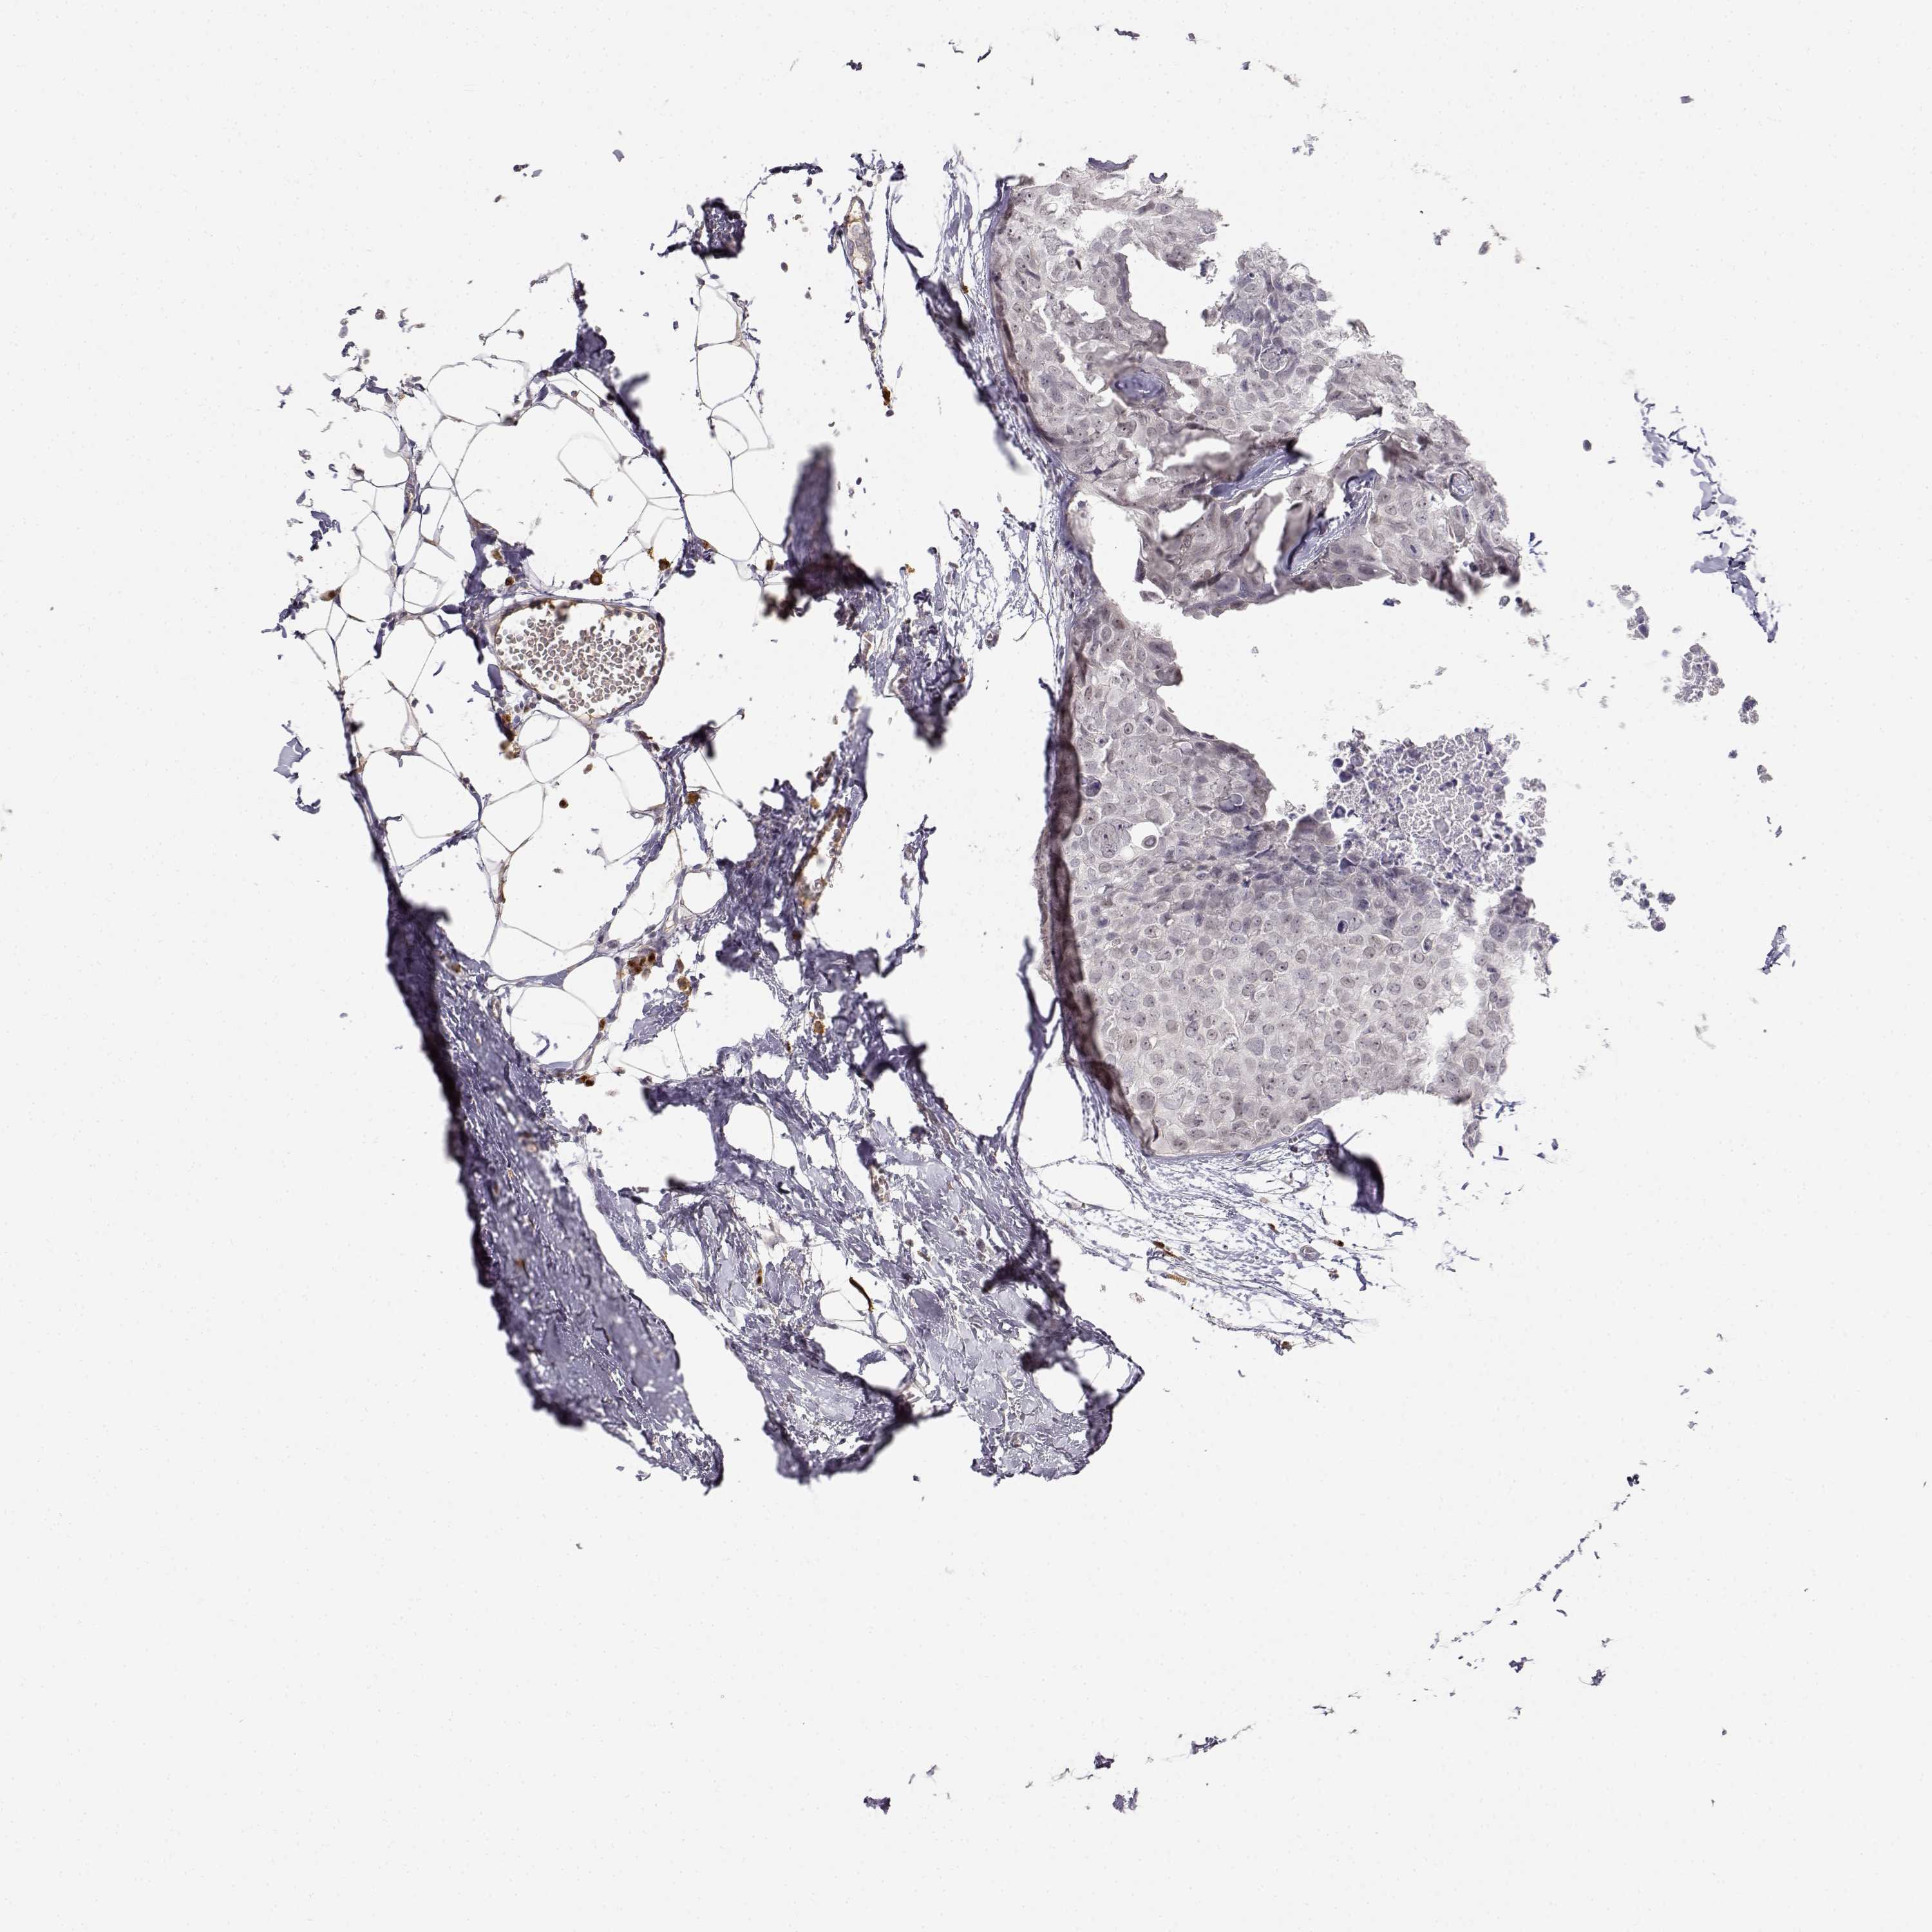

CANCER BREAST CANCER Show tissue menu

BRCA TCGA BRCA VALIDATION PROTEIN EXPRESSION